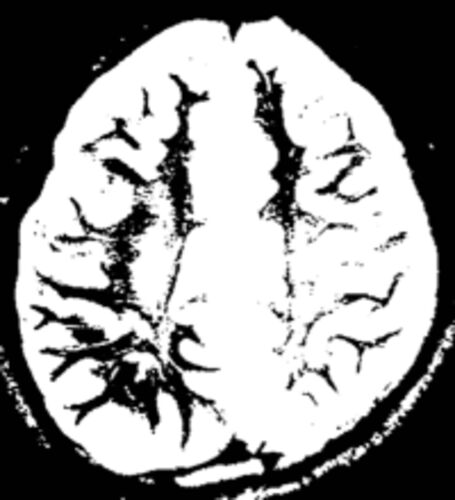

上の画像⬆は、世界で初めての「脳内科医」加藤俊徳医師による右利き(左側)と左利き(右側)の人のMRI画像の比較写真だ。黒く写っている部分が、脳が使われて成長していることを示しているという。つまり、上の画像で黒い部分が多い左利きの人は、黒い部分…